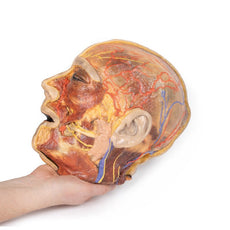

3D Printed Brain Hemisection

This 3D model is a midsagittal hemisection through a whole brain, preserving the right side anatomy and deep brain

structures and spaces visible in the midline. In lateral view, the right cerebral and cerebellar hemispheres are

covered in the arachnoid mater. In the midline view, the brain regions from the cerebrum to the medulla oblongata

are preserved. Centrally, the third ventricle is opened, with an intact septum pellucidum superiorly positioned and

obscuring the lateral ventricles within the cerebral hemisphere. On the inferior margin of the third ventricle both

the right mamillary body and right optic tract can be observed, whereas posteriorly the cerebral aqueduct can be

observed extending across the midbrain between the tectum and tegmentum towards the fourth ventricle (between the

cerebellum and pons). The cerebellum is separated from the occipital lobe by a preserved portion of the tentorium

cerebelli, and in cross-section the cerebellar cortex helps form the prominent arbor vitae.

A series of arterial

branches have been false coloured to contrast their course across the preserved brain structures. In the midsagittal

view the anterior cerebral artery courses from around the corpus callosum to supply the cingulate gyrus and other

midline cortical regions. The base of the middle cerebral artery can be seen passing deep between the temporal and

frontal lobes, with the posterior communicating artery connecting it to a small remnant of the posterior cerebral

artery. Adjacent to the posterior cerebral is the superior cerebellar artery, extending laterally to pass between

the temporal lobe and the cerebellum before passing deep into the transverse fissure.